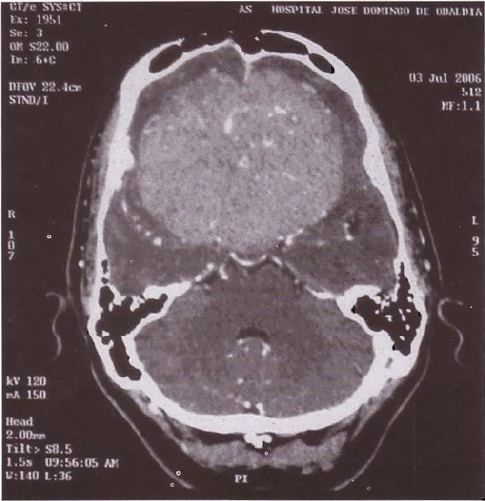

Infección por el Virus de Inmunodeficiencia Humana, Síndrome Antifosfolípido e Isquemia Cerebral: ¿Existe una Relación?

Ana Belén Araúz R., Nuvia Batista R.

4

Síndrome de Foster Kennedy: Reporte de un Caso.

Gerardo Domínguez Vega

8